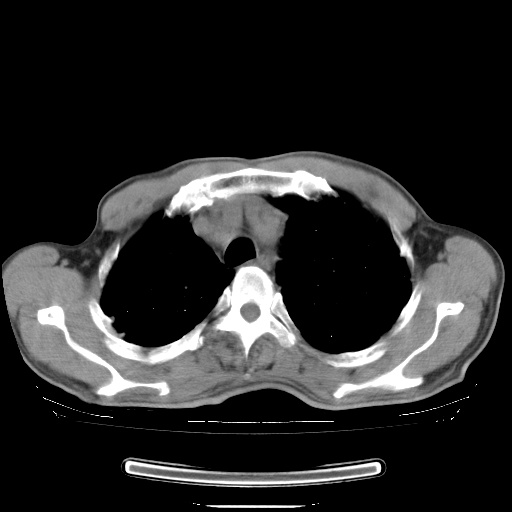

男性患者,63岁。右侧胸背部疼痛2月,加重一周。

还有纵隔多处肿大淋巴结及肋骨的改变、两肺多发结节灶。

考虑右中心型肺癌并右下肺不张,肺及纵隔,左肋骨转移。

右肺下叶中心性肺癌并纵隔淋巴结转移,左侧肋骨转移。双肺上叶继发性结核表现。

1)右肺下叶中心性肺癌并纵隔淋巴结转移,两肺转移,左侧肋骨转移。2)双肺上叶继发性结核。

右肺下叶中心性肺癌并纵隔淋巴结及两肺、左侧肋骨转移。双肺上叶继发性结核表现。